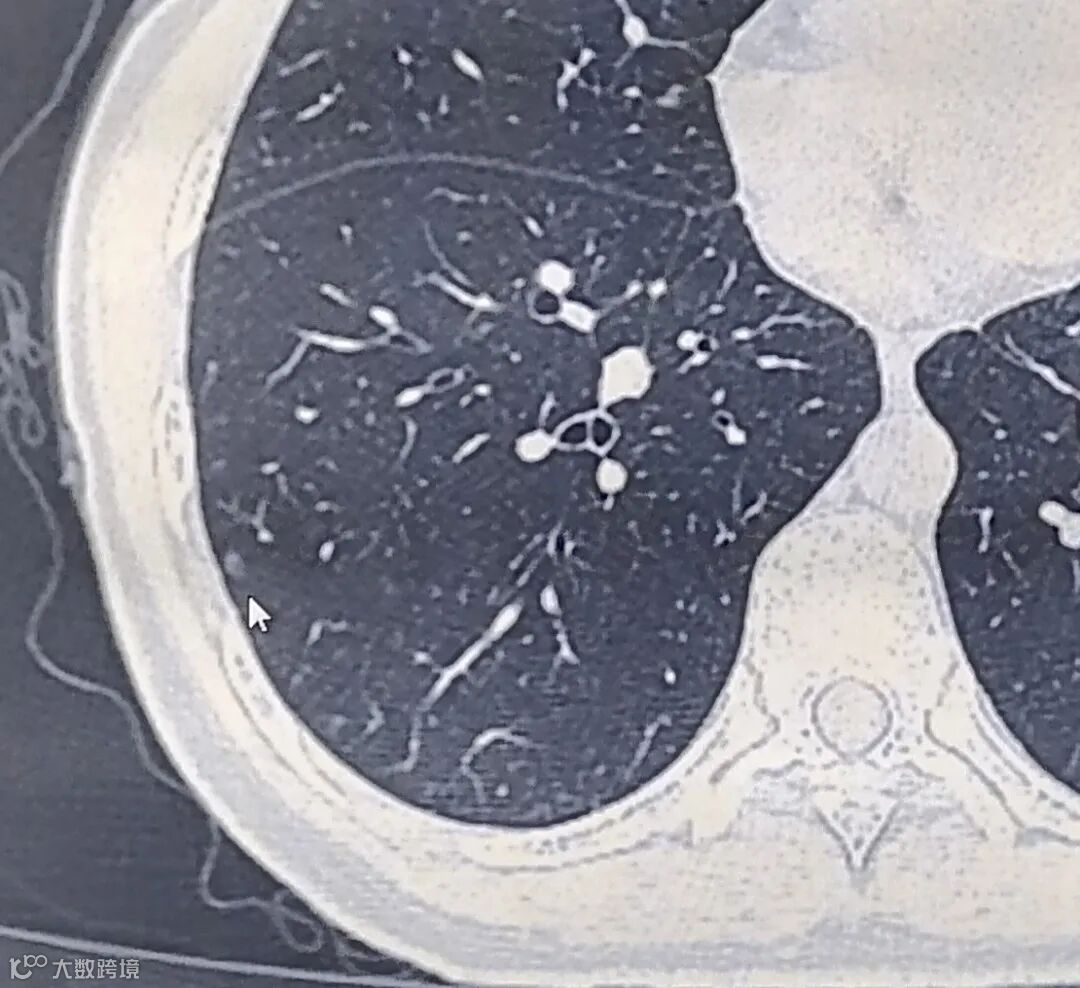

肺结节(pulmonary nodule)是指肺内直径小于或等于3cm的类圆形或不规则形病灶,影像学表现为密度增高的阴影,可单发或多发,边界清晰或不清晰的病灶;小于1cm的被称为肺小结节,而小于5mm的结节称为肺微小结节。

根据肺内小结节的密度可以分三类:

①实性结节

②部分实性结节

③磨玻璃结节

不同密度的肺结节,其恶性率也不同,其中部分实性结节的恶性率最高,其次为磨玻璃结节和实性结节。